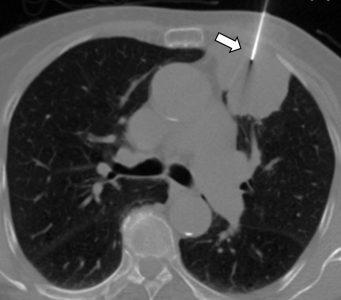

Η διαδερμική βιοψία είναι μια ελάχιστα επεμβατική μέθοδος λήψης υλικού από τον όγκο για κυτταρολογική και ιστολογική εξέταση από εστιακές αλλοιώσεις του ήπατος, του πνεύμονα, του μαστού, του νεφρού κλπ. Συνιστάται από τον κλινικό ιατρό ανάλογα με το είδος και το μέγεθος της βλάβης και πραγματοποιείται με ασφάλεια από επεμβατικό ακτινολόγο συνήθως με την καθοδήγηση αξονικού τομογράφου ή υπερήχων. Στη σύγχρονη ογκολογική θεραπεία, όπου γίνεται προσπάθεια καταπολέμησης του καρκίνου σε μοριακό επίπεδο, κρίνεται αναγκαία η ακριβής ιστολογική ταυτοποίηση του όγκου, ώστε να εφαρμοσθεί εξατομικευμένη θεραπεία για το βέλτιστο αποτέλεσμα.